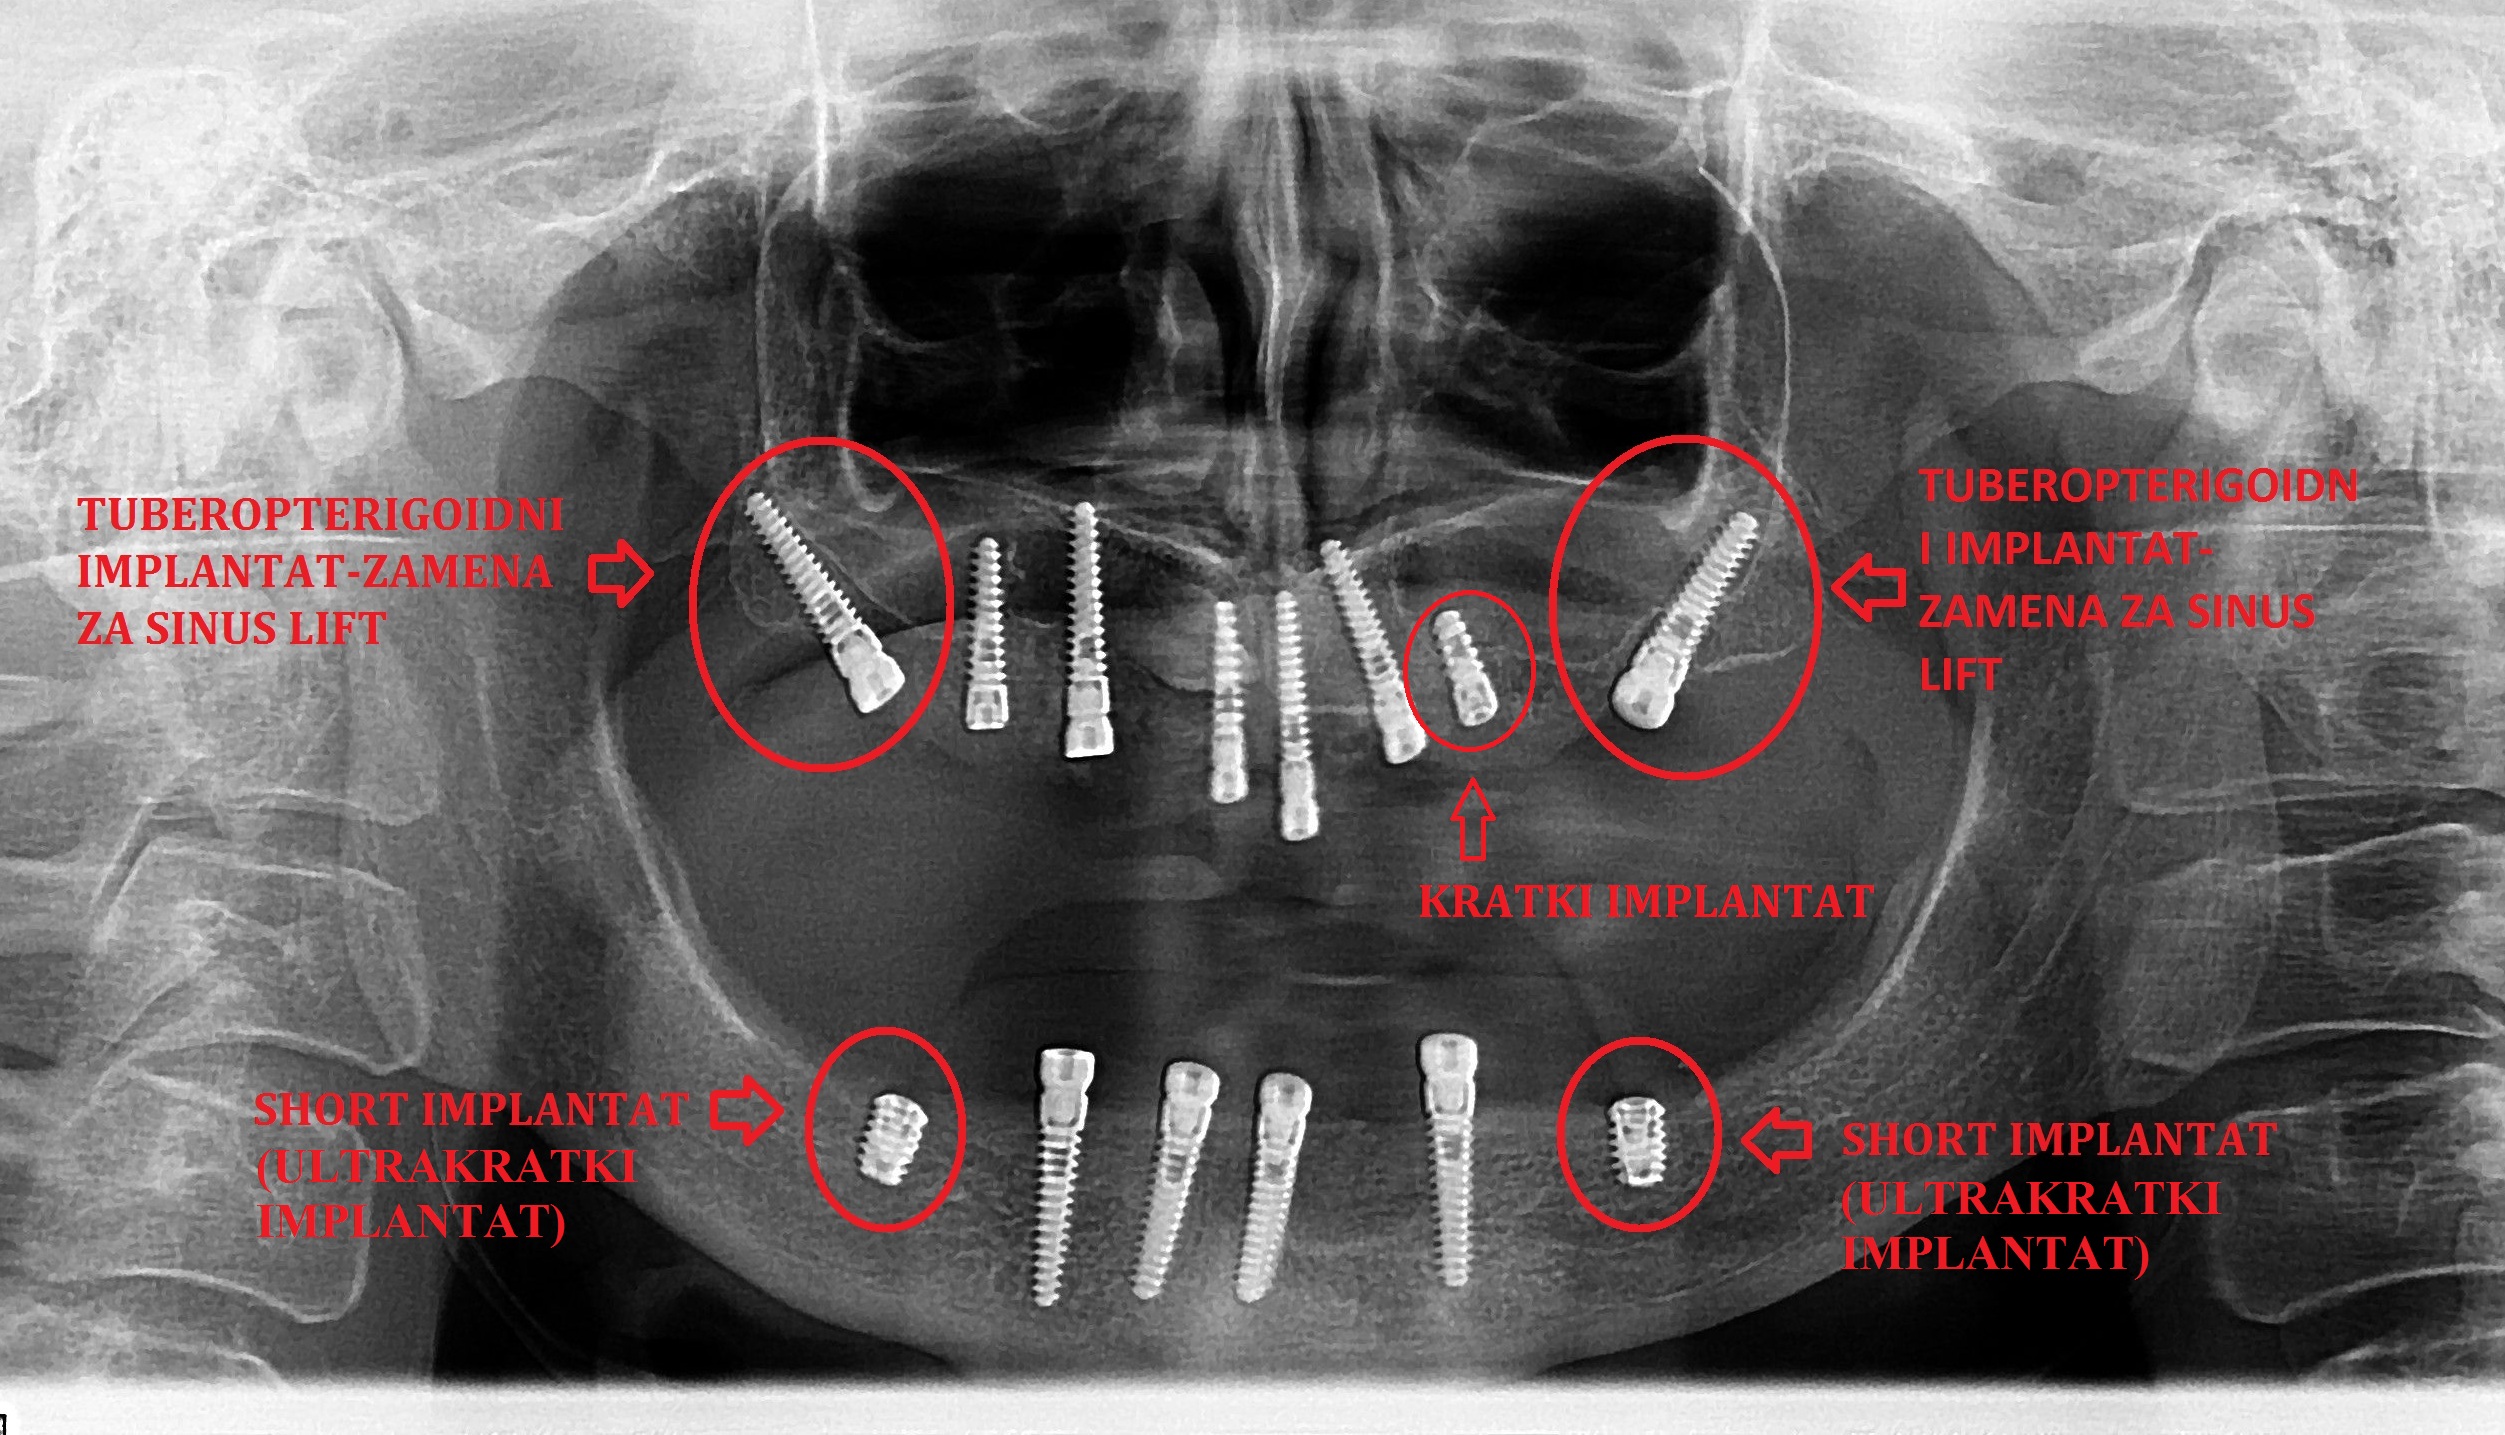

Tuber-pterigoidni implantat bez sinus lift procedure

Dentalna implantologija obuhvata hirurške procedure koje imaju za cilj funkcionalnu rehabilitaciju pacijenata upotrebom dentalnih implantata, odnosno metalnih elemenata koji se hirurški ugrađuju u gornju i donju vilicu.

Implantati mogu da imaju različiti oblik, mogu da se ugrade u različitim pozicijama i različitim tehnikama. Trenutno se većina implantata izrađuje od titanijuma.